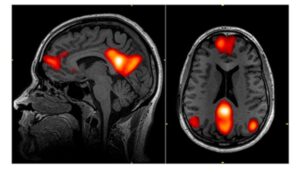

解離性同一性障害では、人格が変わると脳活動も変化することが研究で示されている。

安静時の脳活動を調べた研究では、トラウマに関連した人格では、自己意識に関わる脳領域(背内側前頭前野)と運動・感覚に関わる脳領域(一次運動野、一次感覚野、前補足運動野)の活動が強くなることが分かっている(Schlumpf et al., 2014)。